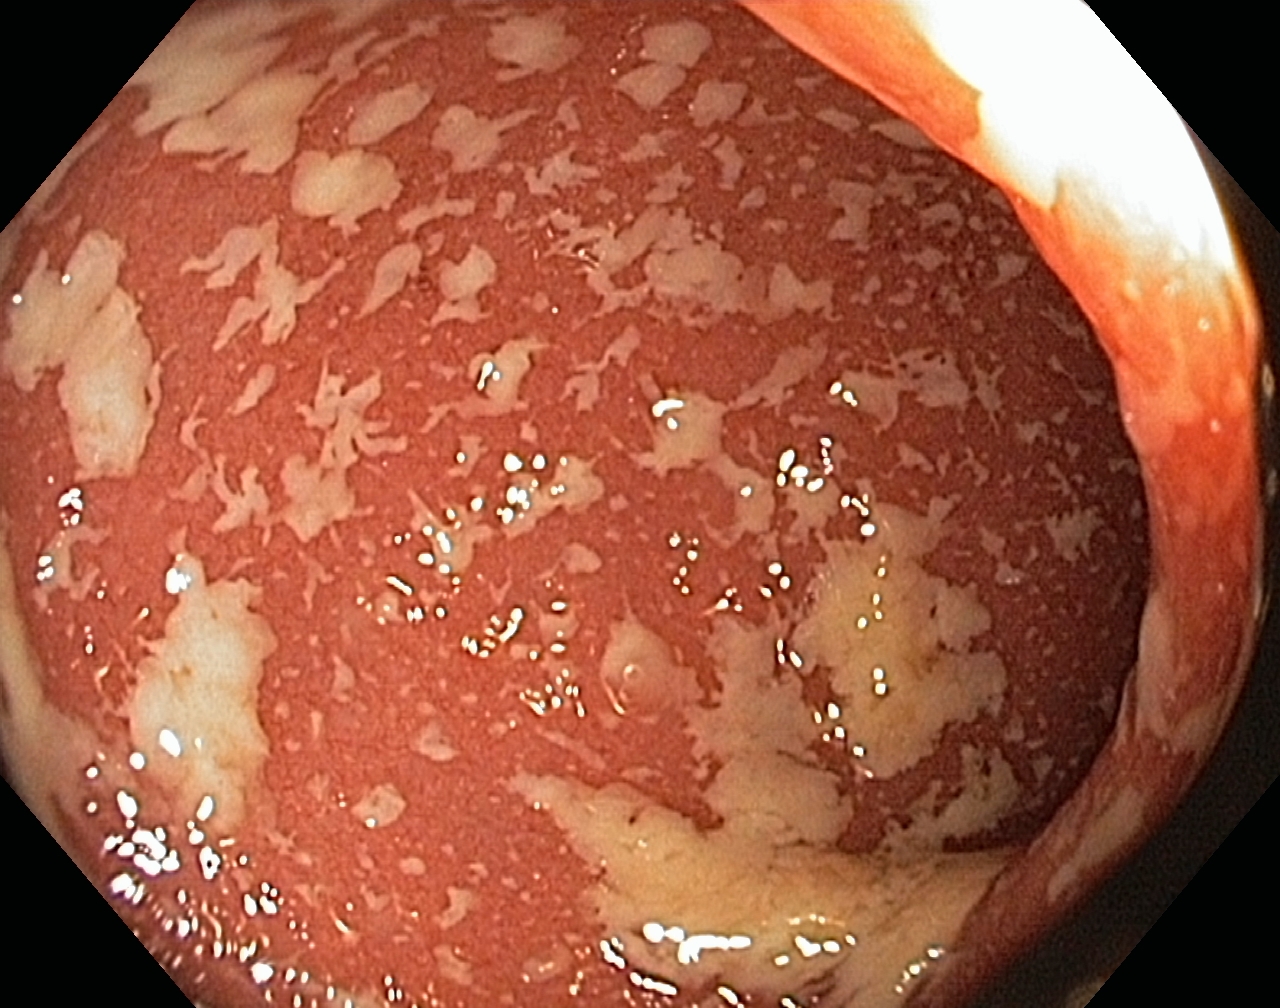

A Distal Ulcerative Colitis